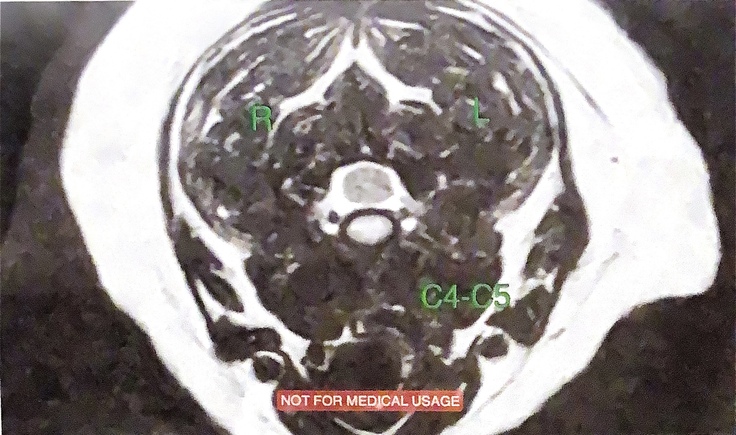

地元の病院では手術していただける病院がなくMRI撮影をしていただいた病院で

岐阜大学動物病院神経科を紹介していただきました。岐阜大学動物病院での診断は下記の画像になります。手術はリスクが高すぎしない方が良いとの事です。治療方針は、放射線治療により、癌の縮小、神経の圧迫解除による、自立歩行、排尿、排便を目指し。出来る限りの延命をめざします、

神経に浸潤した、癌と骨は手術で取り除く事は、極めて難しく、、、